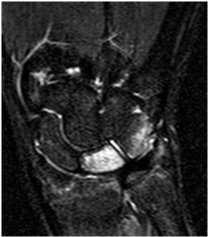

Plain radiographs, computed tomography (CT) and magnetic resonance imaging (MRI) findings revealed multifocal intra-osseous cysts and lunotriquetral AVN (Figure 1, Figure 2 and Figure 3).

Figure 3: Coronal short tau inversion recovery (STIR) image: High signal change in lunate-triquetrum, indicating extensive marrow oedema consistent with AVN. View Figure 3